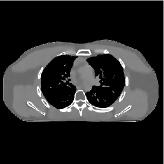

Fig. 7 studies the influence of regularization parameters and on PWLS-ST-. Given a fixed hard-shrinkage parameter , a larger value better removes noise (or unwanted artifacts), but too large can oversmooth reconstructed images; compare Fig. 7(a) and Fig. 7(b). Given a fixed regularization parameter , a larger value leads to lower sparsity in sparse codes and achieves better noise reduction, but too large can remove some edges (e.g., in bone regions); compare Fig. 7(c) and Fig. 7(d). In particular, Fig. S.8 in the supplement shows that once the value is properly chosen, PWLS-ST- is robust to a wide range of values.